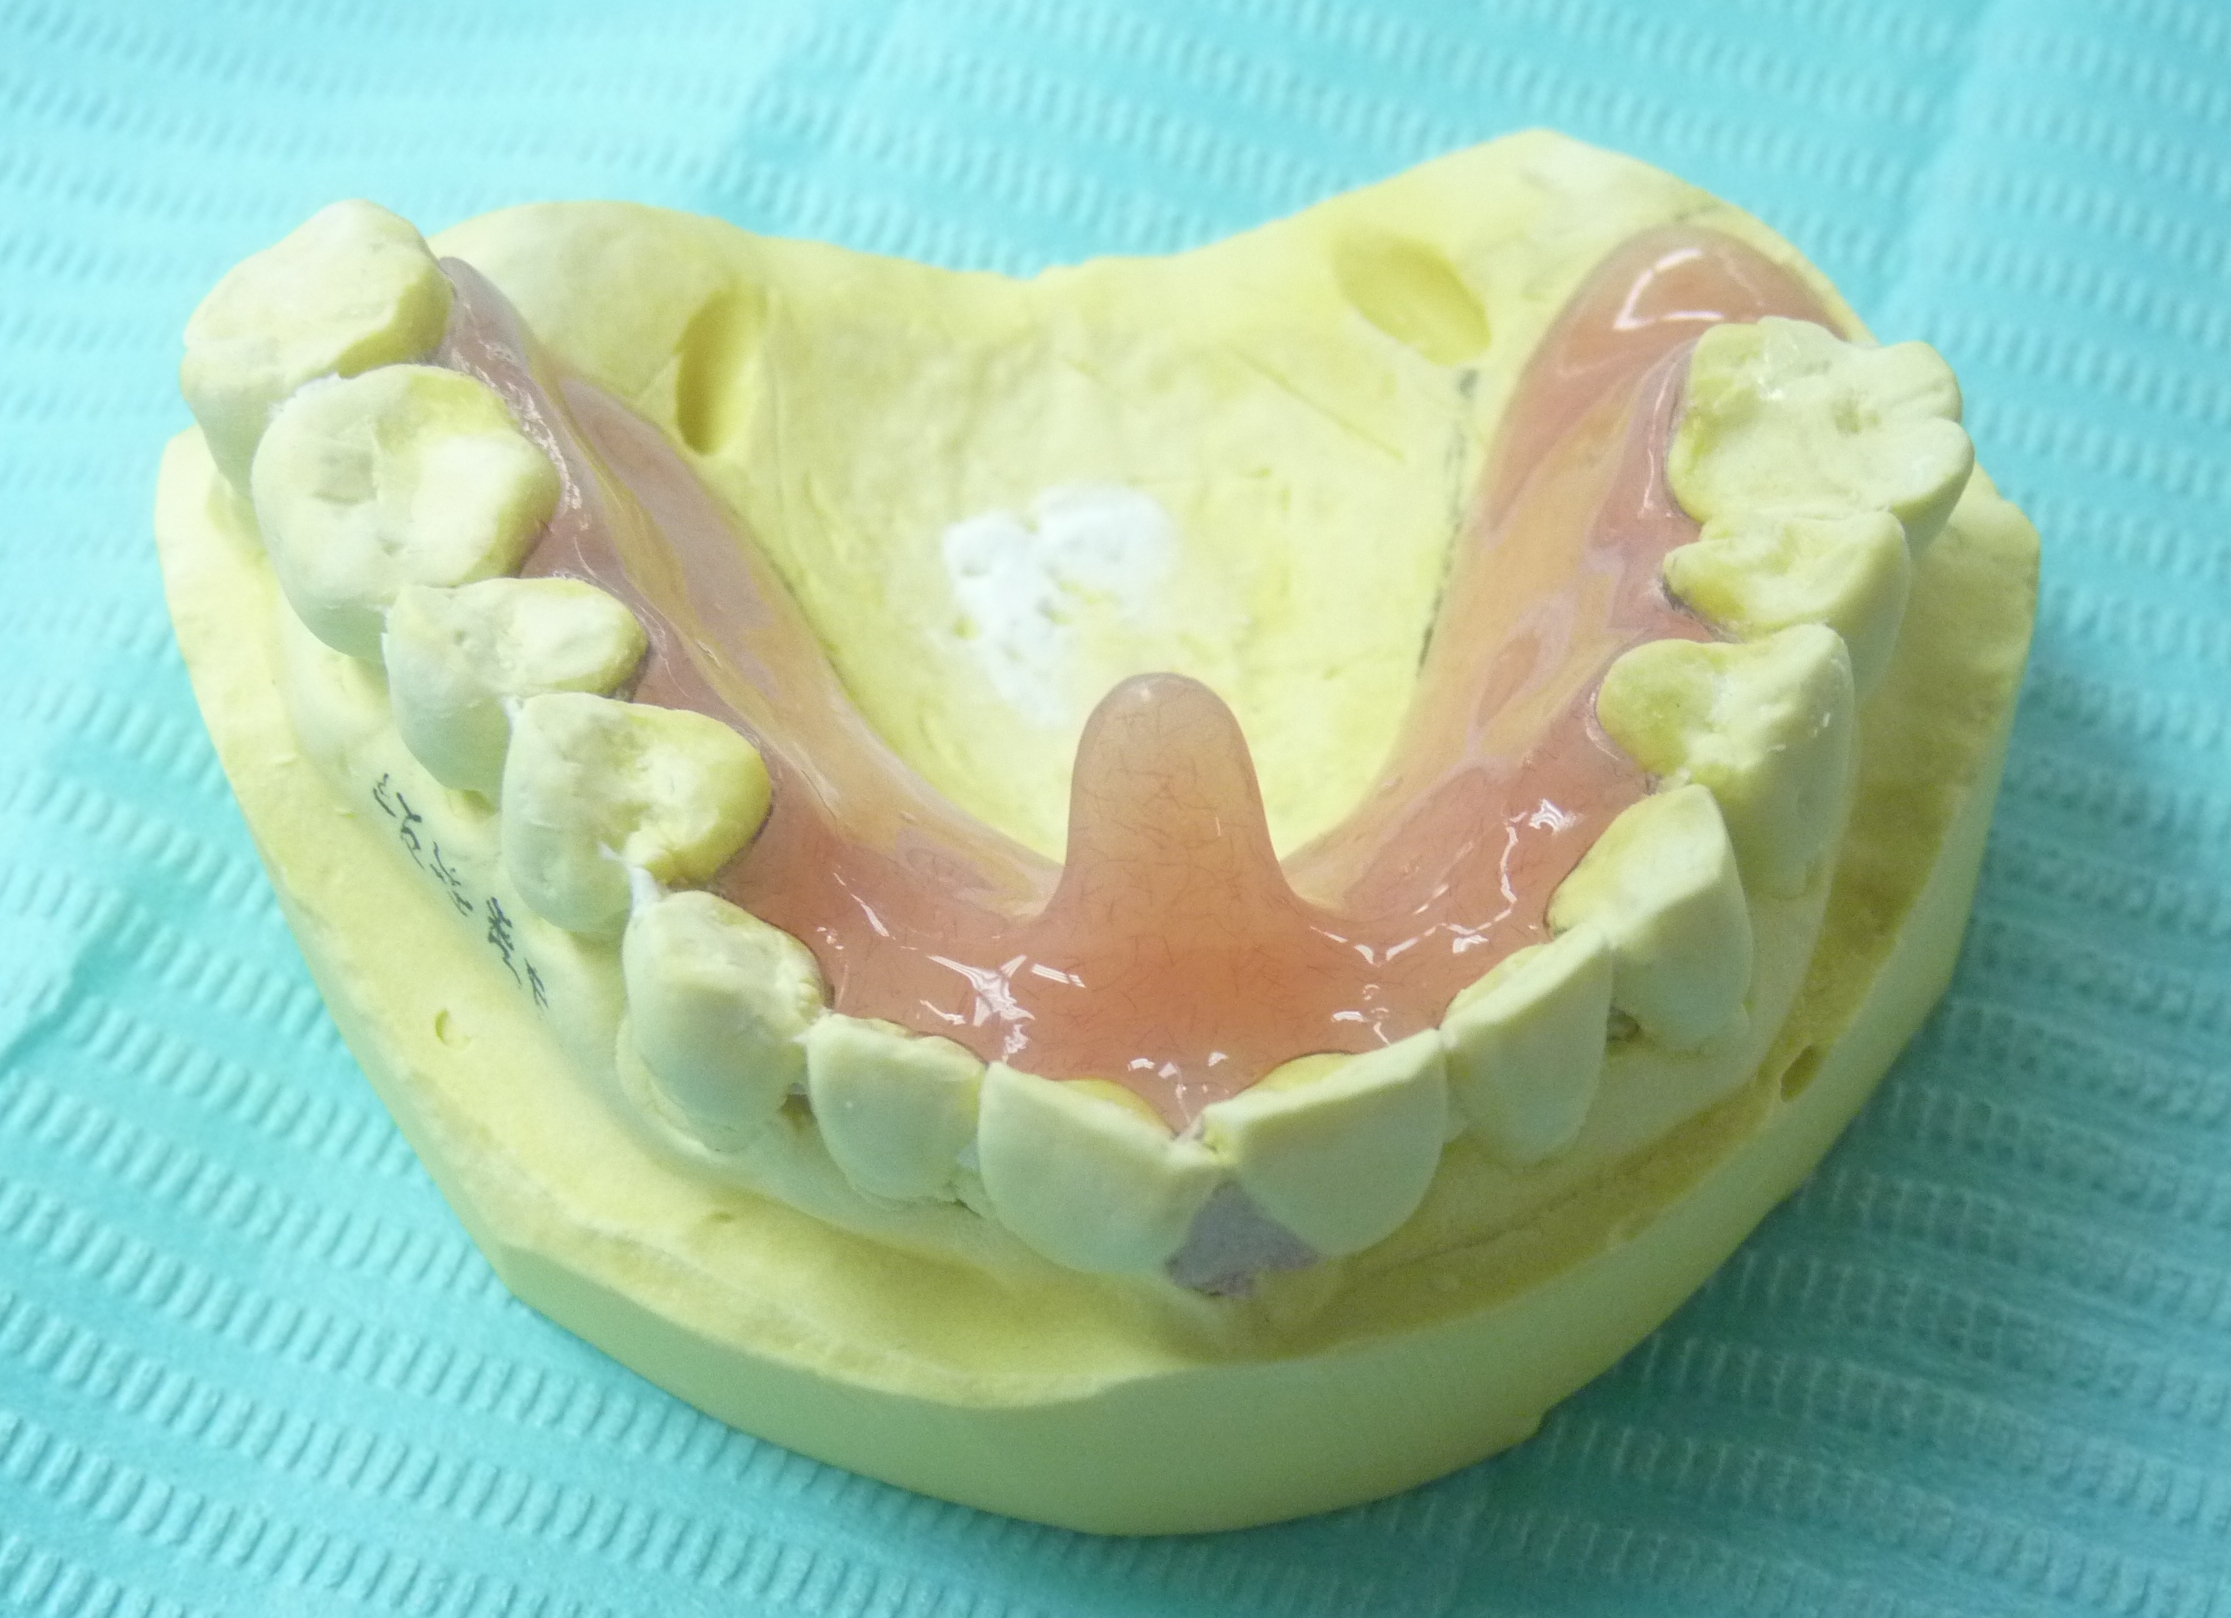

私の先代メインTPC (即時重合レジンで直接法で作成)

(2019/4/1追加) 最近のTPC 突起が長くなってきました

TPCの突起部について質問されたので説明します

とは言っても超簡単なんですが・・・

下の歯に全く当たらない位置と高さに設定するだけです

できるだけ切歯乳頭付近で、下顎前歯に当たらない位置から

できるだけ後下方に伸ばして7ミリ以上の長さになれば完璧です

7ミリ以下でもダメではありません。できるだけ長くでけっこうです

バイトが深い人、後方運動距離の長い人の場合は長さも形態も制約されますが

仕方ないので制約された中形態を決めます

守るべきは絶対に下顎歯に当たらないことです

難しく考えることはないです

まず作ってみて、問題があれば口腔内で削除、添加すればいいですから・・・

ただ、最後に舌に好かれるよう研磨はしっかりして下さい

もっと詳しい作成法は下にある「TPCの作り方」をご覧下さい

このたび義歯床用アクリリック樹脂(加熱重合レジン)を用いて義歯と同じく埋没法で作るように変更しました

外形などは全く変更ありませんので、ワックスアップしてから石膏で埋没します

割り出し以降は変わりません

技工作業をシンプルにするために色付けはせず透明です

作業模型を割らずに割り出した方が後の調整は楽です